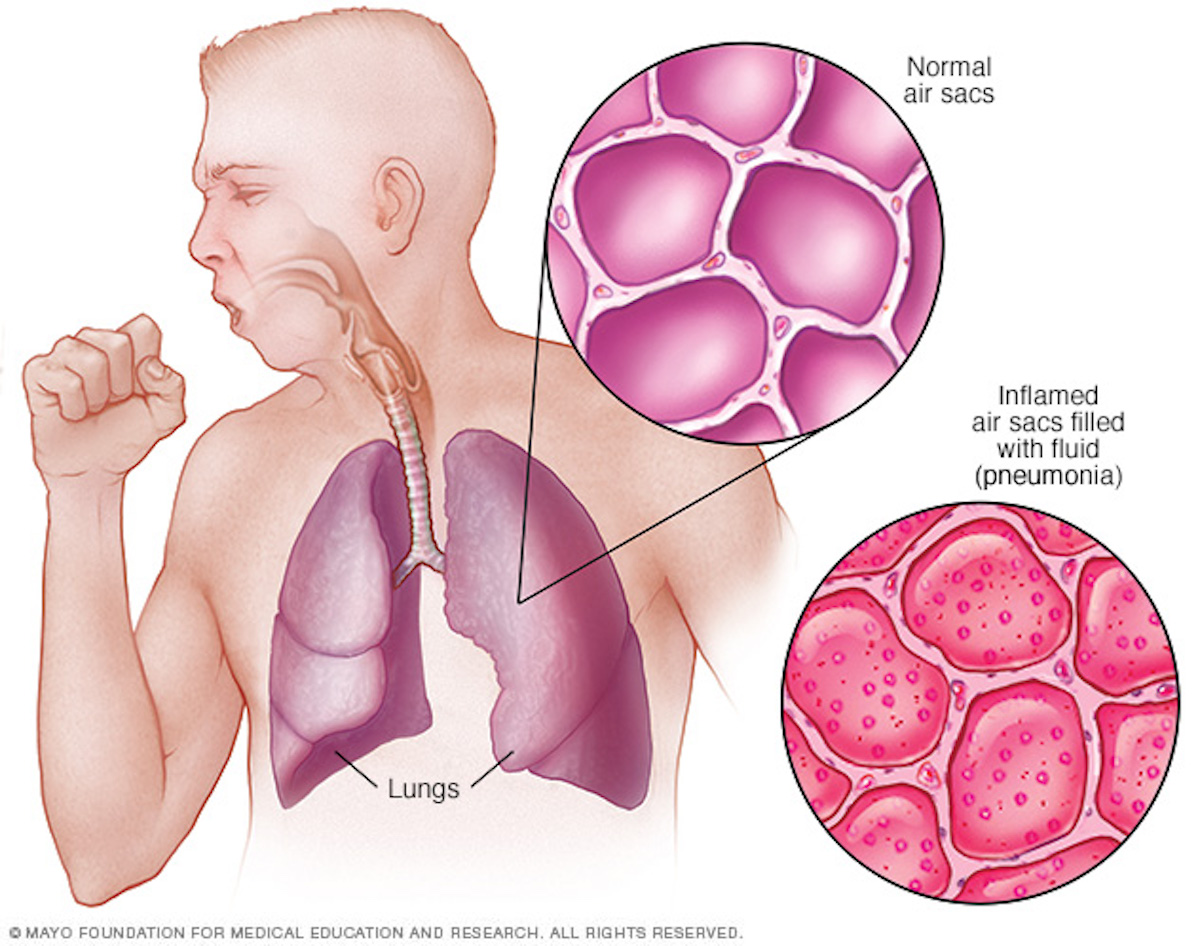

Пневмония - это серьезное заболевание легких, которое может быть вызвано различными причинами, включая бактериальные, вирусные и грибковые инфекции. Для того чтобы наглядно показать симптомы, диагностику и лечение этого заболевания, картинки могут быть очень полезны.

Картинки с симптомами пневмонии

В этом разделе представлены изображения, демонстрирующие различные симптомы пневмонии, такие как кашель, одышка, боль в груди и повышенная температура. Эти картинки могут быть использованы для обучения и презентаций в области медицины и здравоохранения.